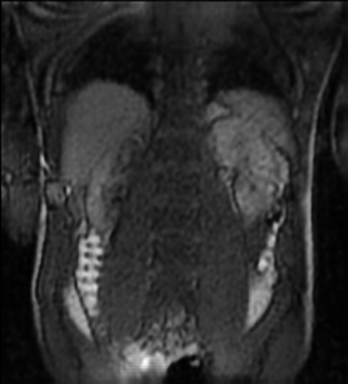

Tables 1 and 2 show our quantitative results: PSNR between the style (image we want to transfer style from) and generated image, SSIM and MS-SSIM between the content (image we want to take structure from) and generated image and finally, our proposed weighted SSIMs. For each style transfer direction and metric, our method consistently outperforms the other approaches. Figures 2 and 3 qualitatively highlight the good results of our method on 2D and 3D datasets. In addition, quantitative results on both figures show that our proposed metric preserves qualitative ordering of results for both style and content. In comparison, metrics such as SSIM struggle to accurately correlate to visual results.

Qualitative evaluation shows that the proposed method leads to sharper images, better content preservation, better localised CE and realistic MRI appearance. Quantitatively, we outperform the other algorithms with each metric, for each style transfer direction. While we expected that adding CE to images would be an easier task than removing CE, we found that for both tasks the method exhibits similarly performing quantitative and qualitative results. The results for style transfer with the kidney data show that when there is clear CE, it is easier to perform style transfer in both directions. However, when style transfer is performed on the prostate data, the model struggles in comparison to the kidney data. This may be due to the enhancement of the prostate being less defined than the kidney data. In figure 3(b), we can see the prostate with CE. Compared to figure 2(b) showing kidneys with CE, it is harder to determine the edges. The two original images shown in figures 3(a) and 3(b) are clear and easy to see some edges of prostate, in other images, it is harder to see the edges of the prostate.

(C) CW-SSIM: 0.39

(S) CW-SSIM: 0.29

(C) CW-SSIM: 0.53

(S) CW-SSIM: 0.31

(C) CW-SSIM: 0.42

(S) CW-SSIM: 0.54

(C) CW-SSIM: 0.93

(S) CW-SSIM: 0.62